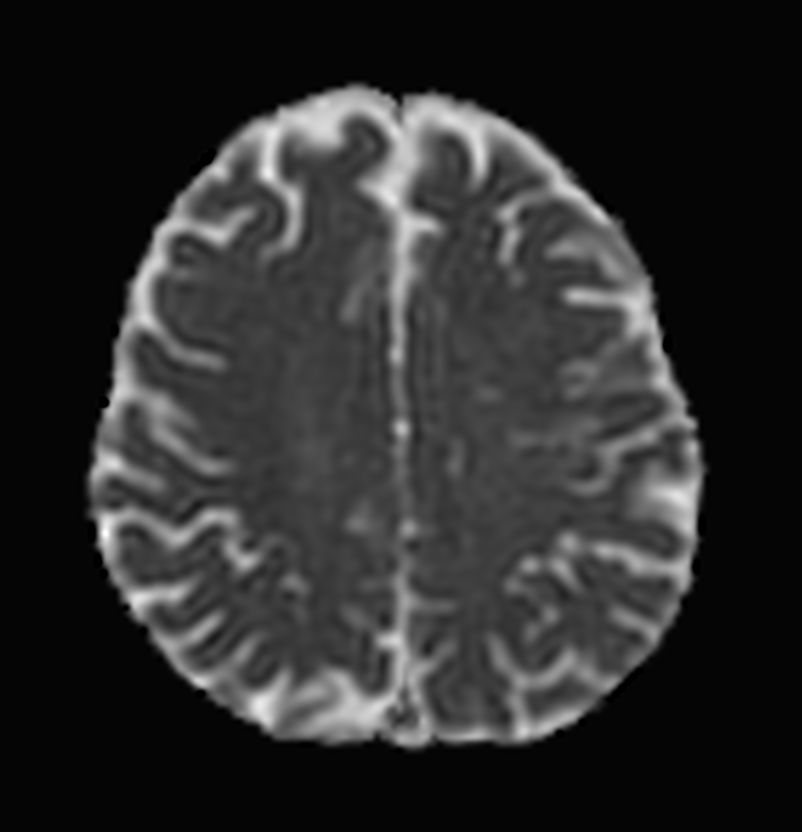

Brain small infarction

Patient with a small brain infarction. Compressed SENSE acceleration is used to speed up sequences while maintaining equal image quality. Three different diffusion methods are included; A fast 52 secs DWI EPI sequence, a high resolution DWI EPI sequence and a TSE based DWI sequence. A SWIp sequence is included offering high resolution 3D susceptibility weighted imaging to enhance contrast for deoxygenated (venous) blood or calcium deposits. 3D APT sequence is included providing contrast-free brain imaging, addressing the need for more confident diagnosis in brain neuro oncology by using the presence of endogenous cellular proteins to produce an MR signal. And a large FOV TOF MR Angiography sequence is included to check on brain vascular anatomy.

Axial DWI EPI (b1000)